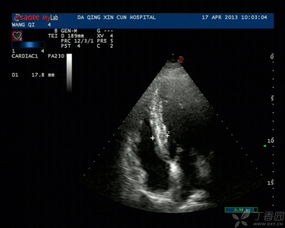

血流信号,即血流的丰富程度。

血流丰富程度的分级通常分为四级:

0级为肿块内未见血流信号显示;

1级为少量血流,肿块内见1~2个点状血流信号;

2级为中量血流,肿块内见3~4个点状血流信号或一条管壁清晰的血管;

3级为丰富血流,肿块内见4个以上点状血流或2条管壁清晰的血管。

一般来说,恶性肿块的血供较良性肿块丰富,前者多为2~3级血流,后者多为0~1级血流。肿瘤中,恶性组2~3级血流的占86.96%,良性组0~1级血流的占91.3%。

虽然血流丰富程度与良恶性有关,但与肿块的大小亦有一定的关系。一些较大的乳腺良性肿块内可观察到丰富的血流信号,而在一些小乳腺癌内却未见血流信号显示,这可能与肿瘤体积小,新生血管相对较少且管径较细,以及仪器的灵敏度的局限性,以致细小血管的低速血流难以显示等因素有关。

CDFI显示人体的血流,二、三维超声成像显示人体的解剖结构,二者提供了完整的人体解剖信息。以CDFI为基础,由于CDFI不需要方向分离、频域解调等处理,可降低检测阈值,便于显示小血管中的低速血流,但不能区分流向和流速。